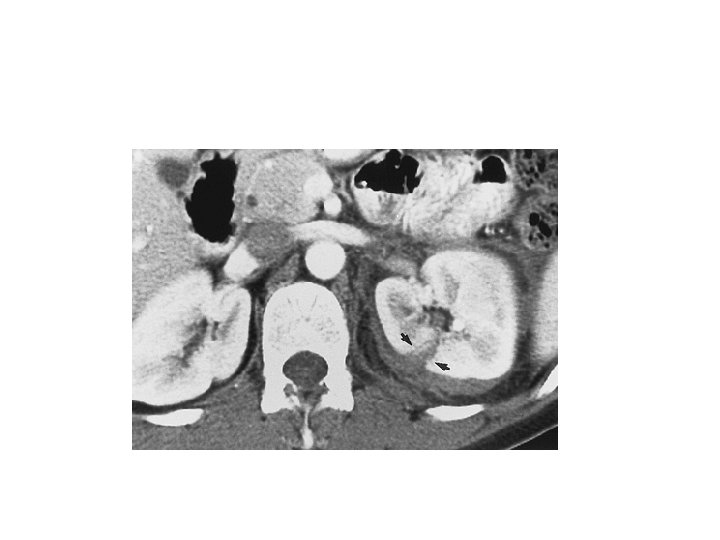

Whom to work up • Penetrating trauma: EVERYONE • Pediatric patients with microscopic hematuria. • Blunt trauma: Image with CT if: • gross hematuria • microhematuria plus shock • microhematuria plus acceleration/deceleration Mee et al. (1989) Hardeman et al (1987

Imaging of trauma patient with hematuria • CT preferred – With contrast – With “delayed” films (mandatory) – Why not get CT cystogram too? • Standard intravenous pyelogram (IVP): Forget it • “One Shot” intraoperative IVP – 2 cc/kg intravenous contrast – Single film at 10 minutes

Intraoperative One Shot IVP • Allows safe avoidance of renal exploration in 32% (Morey et al, 1999) • Highly specific for urinary extravasation • Confirms existence of the other kidney